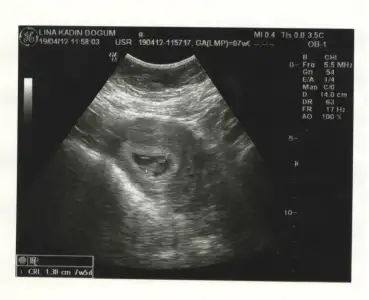

ultrason fotosu koyma fikri benimdi ama hala koyamadım özür dilerim,,şimdi hemen ekliyorumm..

doktor macerama gelince,,bana idrarımı tutmam gerektiği söylenmediği için ultrasonda bebeğimi göremedik,alttan ultrason oldu..ordan baktık...kalp atışlarını duymak inanılmaz güzel ve çok hızlı atıyor,20 gün sonra tekrar gideceğimm işte benim fasülyem..bu aralar çok halsizleşmeye başladım ve mide bulantım var ama kusmadım

Eki Görüntüle 395009 Eki Görüntüle 395010 Eki Görüntüle 395009 Eki Görüntüle 395011